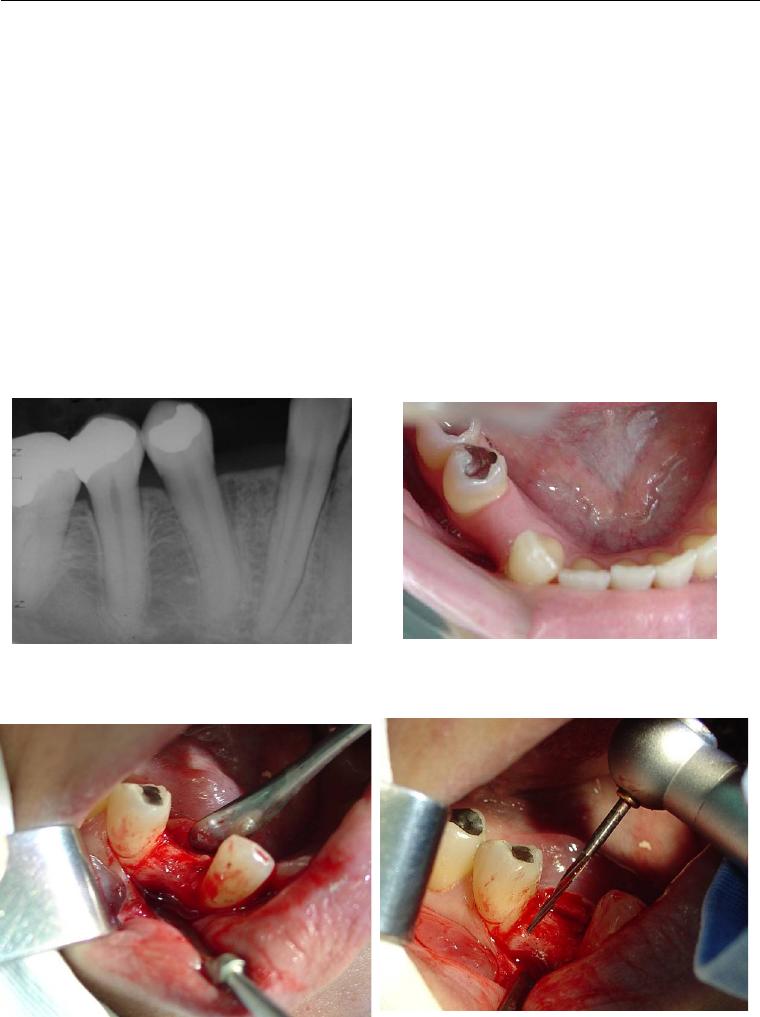

Foi no intuito de transpor estas dificuldades que se idealizou o sistema de

implante inicialmente conhecido como Wedge (figura 1) e que, após dez anos de